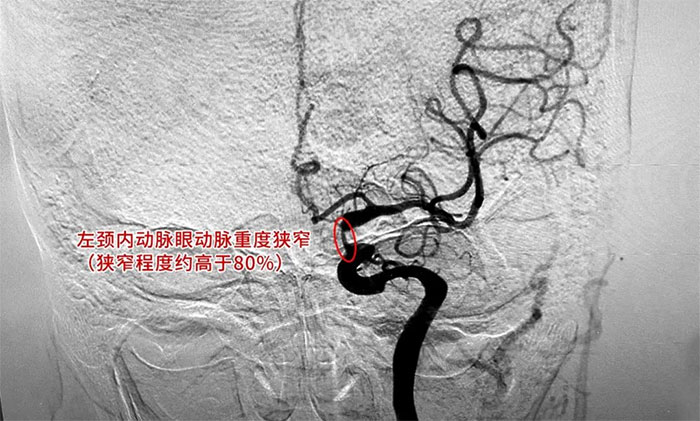

為進一步明確診斷并制定治療方案,周君主任與醫(yī)院學術副院長兼神經內科4A病區(qū)主任席剛明教授對患者病情開展了討論評估,由席教授為患者進行DSA全腦血管造影檢查,造影可見左頸內動脈巖骨水平段中度狹窄,左頸內動脈海綿竇段輕度狹窄,左頸內動脈眼動脈重度狹窄(狹窄程度約高于80%)。

▲ DSA檢查影像